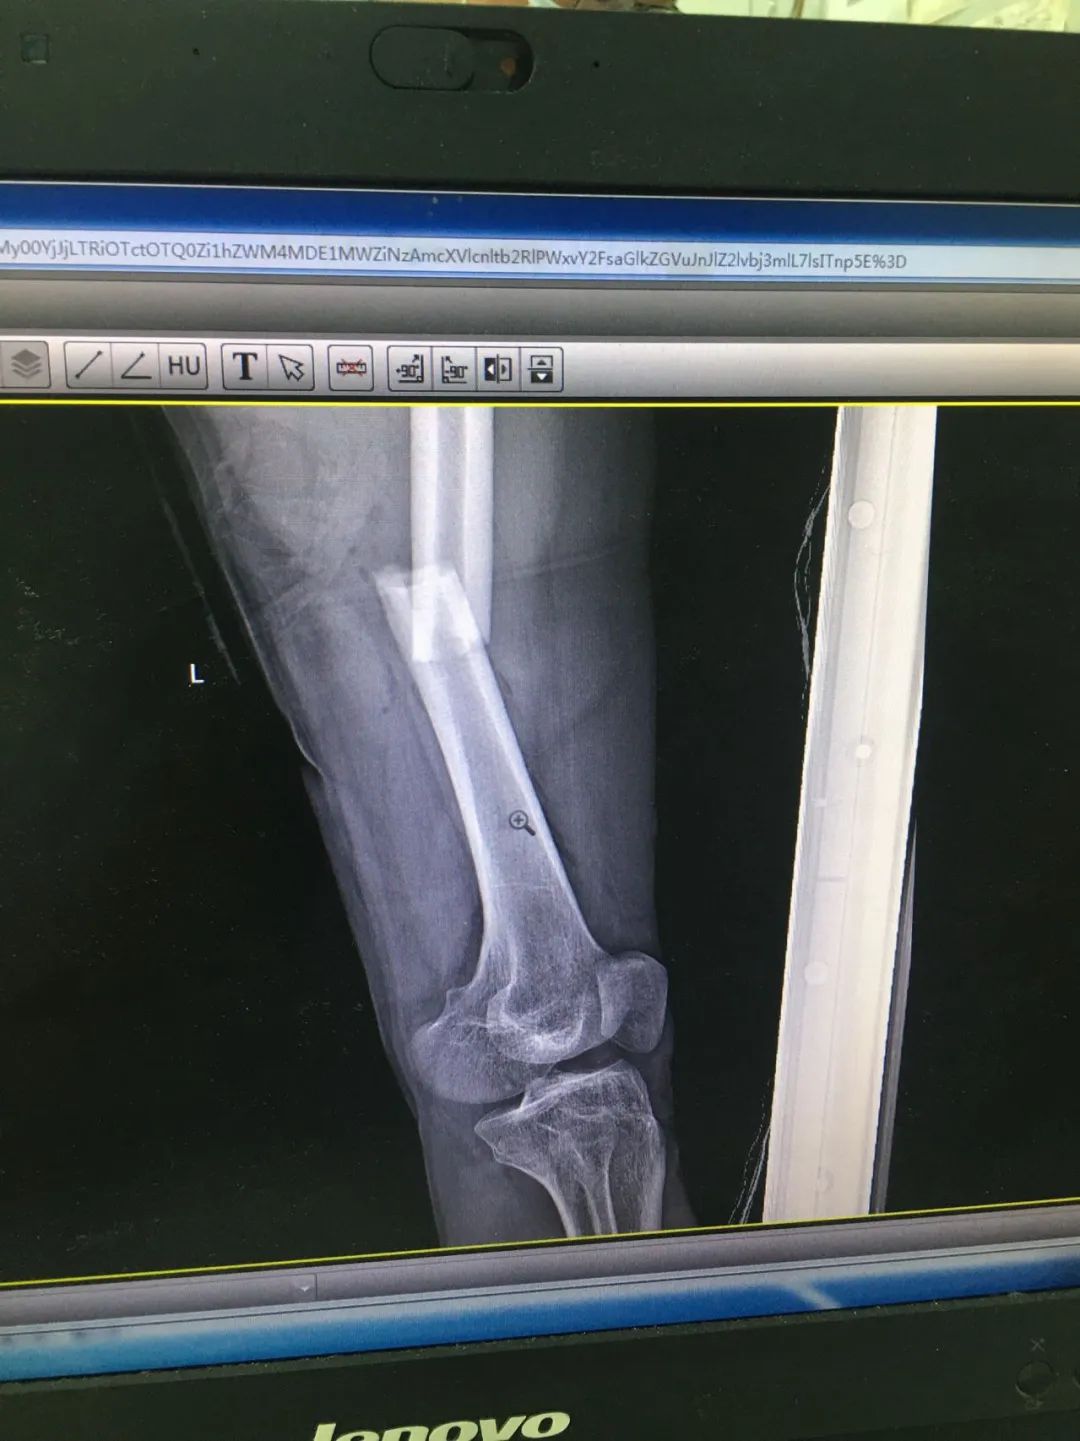

第1次手術(shù)10天后,骨科為劉先生安排了第2次手術(shù),歷經(jīng)3個小時,成功完成左股骨干骨折及左脛骨遠(yuǎn)端骨折閉合復(fù)位內(nèi)固定術(shù),植入兩根30cm×10mm、34cm×10mm髓內(nèi)釘。

術(shù)后一周,患者手術(shù)切口愈合良好,左下肢皮膚感覺及肌力正常,左足末梢循環(huán)恢復(fù),復(fù)查X片顯示骨折復(fù)位標(biāo)準(zhǔn),內(nèi)固定物位置良好。